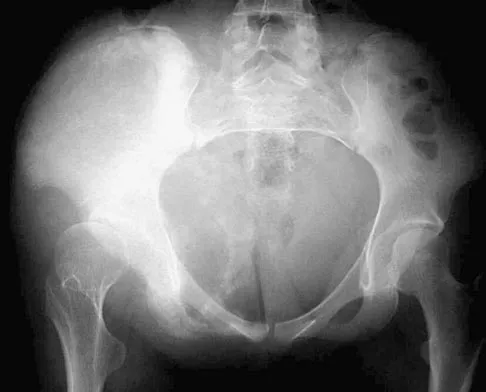

Figure 44 shows the radiograph of an 11-year-old girl who has hip pain. Further diagnostic workup should include

Explanation

The patient has severe acetabular protrusio, a condition that is frequently associated with Marfan syndrome. An echocardiogram is necessary to rule out the most serious consequence of this syndrome, aortic root widening, which can lead to aortic valve dysfunction or fatal aortic rupture. An electromyogram may be indicated for Charcot-Marie-Tooth disease, which is associated with acetabular dysplasia, but not protrusio. The renal ultrasound, the MRI scan, and the biopsy would be of no value in this patient. Protrusio can also be seen in patients with osteogenesis imperfecta and juvenile rheumatoid arthritis. Steel HH: Protrusio acetabuli: Its occurrence in the completely expressed Marfan syndrome and its musculoskeletal component and a procedure to arrest the course of protrusion in the growing pelvis. J Pediatr Orthop 1996;16:704-718.